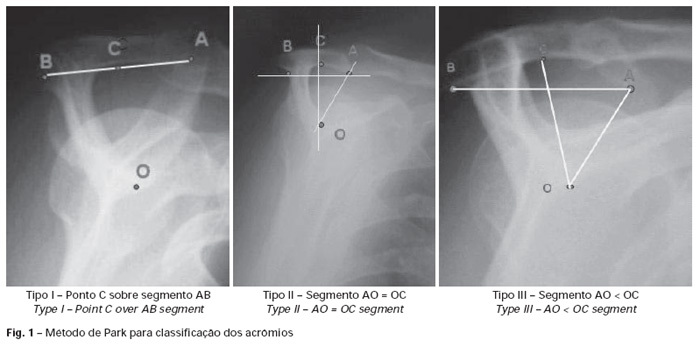

Paciente 42 anos, feminino, procura ambulatório de acupuntura para tratamento de dor no ombro direito iniciada há cerca de 1 ano. Dor em pontada, de forte a moderada intensidade, piora à abdução, irradia para face anterolateral, com restrição a movimentos, prejudica sono. Nega parestesias. Radiografia do ombro mostra acrômio curvado ou ganchoso, com diminuição do espaço da articulação glonoumeral. Qual o diagnóstico mais provável? (TEAC 2013)

A

Síndrome do Impacto do Ombro tipo III

*Acrômio curvado ou ganchoso, com diminuição do espaço da articulação glenoumeral.

https://www.rbo.org.br/detalhes/1026/pt-BR/acromio-em-forma-de-gancho--uma-variacao-anatomica-ou-um-processo-degenerativo-